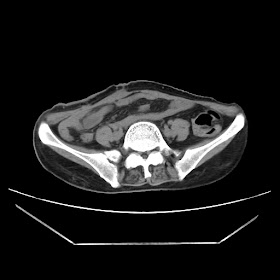

Radiological images:

CT-Scan investigation done on 16Apr16